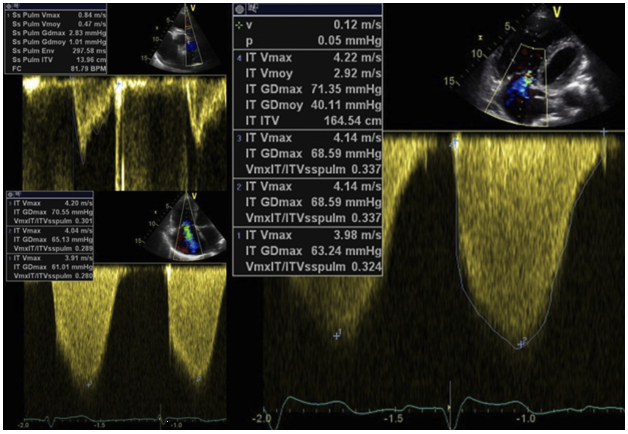

对肺循环而言,其泵血的动力来源少部分为体循环左心室的收缩,而右心室收缩做的功则占绝大部分,故对于肺循环收缩力的评价,我们更多是直接评价右心室的收缩能力(前次文章已经做了相关论述),我们的结论是:三尖瓣瓣环收缩期运动(TAPSE):理论应该大于1.5 cm;RV-TDI下游离壁Sm值理论应该大于10 cm/s;RV dp/dt理论应该大于400 mmHg/s。若测得的相关指标低于上述的理论值,则代表右心室收缩功能的降低,肺循环收缩力的下降。除外整体收缩力的评价,重症超声对肺循环的收缩力评价还可以看右室局部收缩力的大小是否均一,类似右心室的二维层面的斑点追踪技术(STI)来评估右心室局部收缩力的改变,也具有重要的临床意义。肺循环为低压系统,其压力的变化更多来自肺循环阻力的继发改变。对肺循环阻力的评价,除了直接计算肺循环阻力指数外[公式:肺血管阻力(PVR)=三尖瓣反流峰值流速(TRV)/右室流出道速度-时间积分比值(VTI)×10+0.16,参考值为100~250 Wood·m2](图12),我们也可以通过其他一些征象和指标来判断肺循环阻力的改变,这些征象包括心尖四腔心观察到的室间隔矛盾运动,在舒张期室间隔位于受压左移的状态,在收缩期,室间隔又回到右移的状态;在胸骨旁短轴切面,见到半月形的右室开始变得接近圆形,室间隔严重左移使室间隔收缩期呈现“D”字征(图13);心尖四腔心切面测量的三尖瓣反流速度超过3.4 m/s或三尖瓣反流速度在2.9~3.4 m/s之间伴右心肥厚或右室扩张征象。